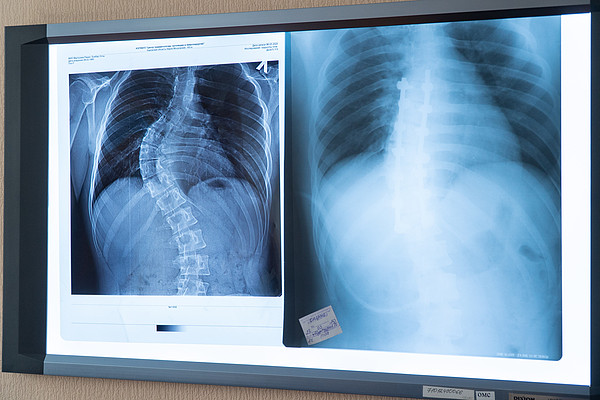

DSC08040.